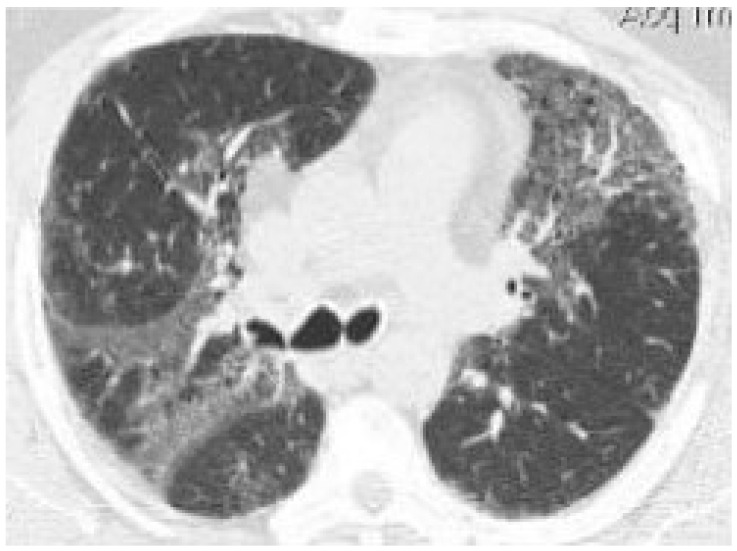

In the nine patients with cannabinoid-positive BAL, we observed ground-glass opacities in four (44.4%), tree-in-bud sign in two (22.2%), bilateral micronodules in one (11.1%), and consolidations in one (11.1%) (Figure 1).

On chest CT, ILD emerged in 4/10 (40%) cases with cannabinoid-positive surgical specimens, and in 0/5 (0%) with cannabinoid-negative surgical specimens (p = 0.2308; 95% C.I. [0.347–∞]). Among the four cannabinoid-positive patients with ILD, we observed ground-glass opacities in one (25%), ground-glass opacities and consolidations together in two (50%), and micronodules in one (25%). At the histological examination, the lung tissue of these four cannabinoid-positive patients with ILD on chest CT scan was characterized by interstitial fibrosis and DIP-like reaction, more specifically, the patient with ground-glass opacities had interstitial fibrosis; the two patients with ground-glass opacities and consolidations and the patient with micronodules all three had DIP-like reaction and two interstitial fibrosis.

Moreover, in Group 1, among the nine patients with chest CT signs of ILD and cannabinoid-positive BAL, the main cannabis-induced organ lesions were ground-glass opacities in 44.4%, tree-in-bud sign in 22.2%, bilateral micronodules in 11.1%, and consolidations in 11.1%. Thus, this evidence would suggest, in cases where these radiological patterns are found, to better investigate the possible use of illicit drugs.

In addition, in Group 2, among the four cannabinoid-positive patients with chest CT signs of ILD, we observed ground-glass opacities, consolidations, and micronodules, again suggesting, in case of these radiological findings, to consider a possible history of illicit drug use.